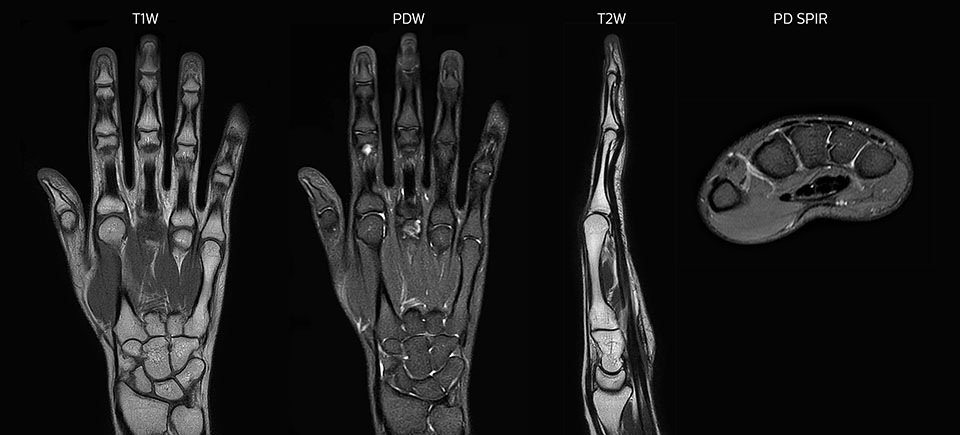

Clinical cases from Radiology Schiffer

MRI of hand and wrist with large FOV

Prodiva imaging of the hand covers the fingertips and includes the full wrist as well. The dS MSK M coil is easy to use.

MRI of the finger

MRI of the finger with high SNR and good resolution in a 10 cm field of view on Prodiva 1.5T. The diagnosis in this 63-year-old patient is bone elasmanosis.